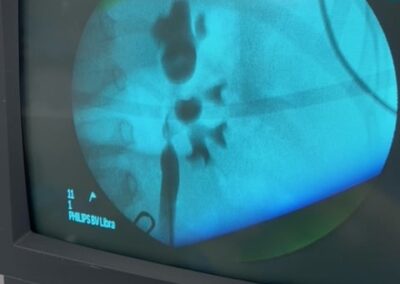

Ο Δρ. Βασίλης Πουλάκης ήταν πάλι όπως κάθε μήνα και τον μήνα Μάρτιο για δύο ημέρες (Δευτέρα 22 και Τρίτη 23 Μαρτίου 2021) στο Ιπποκράτειο Νοσοκομείο στη Λευκωσία της Κύπρου, όπου πραγματοποίησε τέσσερεις ρομποτικές ριζικές προστατεκτομές με διατήρηση των αγγειονευρωδών δεματιών της στύσης και παράλληλα με εκτεταμένο λεμφαδενικό καθαρισμό αλλά και μία αμφοτερόπλευρη διαδερμική νεφρολιθοτριψία (Ultra-Mini PCNL) σε ένα μικρό αγόρι ηλικίας 3,5 ετών με κοραλλοειδείς λίθους και στους δύο νεφρούς.

Η πρωτοποριακή και μοναδική για τα ουρολογικά χρονικά της Κύπρου εξαιρετικά λεπτεπίλεπτη διαδερμική αφαίρεση των ευμεγέθων λίθων και από τους δύο νεφρούς του μικρού αγοριού με μία μόνο επέμβαση-νάρκωση ήταν απολύτως επιτυχής και ο μικρός ασθενής κατέστη ελεύθερος λίθων (“stone free”).

Για την επιτυχή πορεία αυτής της πολύπλοκης και δύσκολης επέμβασης θα ήθελα να ευχαριστήσω όλους όσους, επώνυμα και ανώνυμα, βοήθησαν αλλά κυρίως τους συνεργάτες μου Ουρολόγους, Βασίλη και Νίκο που με στήριξαν σε κάθε βήμα αυτής της περίπλοκης επέμβασης.Παρακάτω οι φωτογραφίες από την ακτινοσκόπηση την ώρα της επέμβασης και η τελική εικόνα με τις νεφροστομίες.